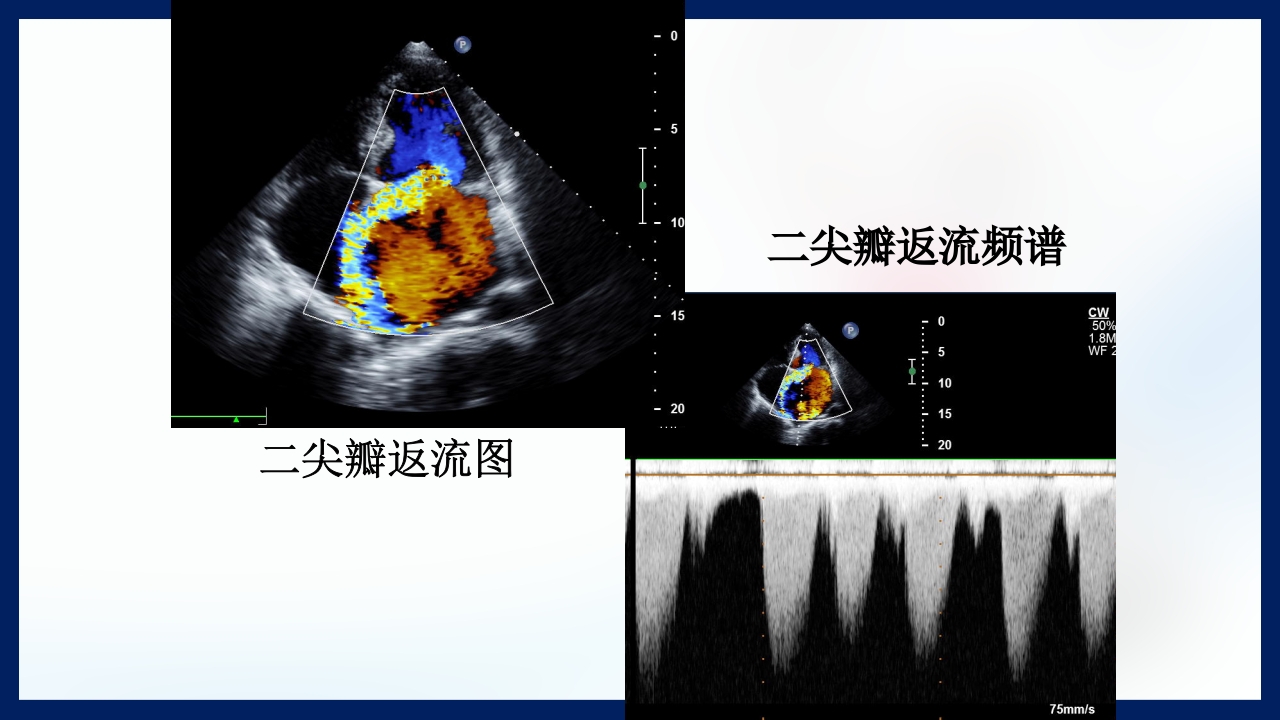

心 脏 瓣膜 医师:XXX 日期:20XX.XX.XX 讲授目的和要求 1 掌握二尖瓣和主动脉瓣膜病变的病理生理、临床表现及诊断方法。 熟悉二尖瓣和主动脉瓣膜病变的病因、鉴别诊断、并发症、治疗原则及 2 手术适应证。 3 了解瓣膜病的检查方法及治疗新进展。 心脏瓣膜病 是由于炎症、粘液样变性、退行性改变等原 因引起的单个或多个瓣膜结构的功能或结构异常,导致 瓣口狭窄及(或)关闭不全。二尖瓣最常受累,其次为 主动脉瓣。 (Rheumatic Heart Disease)简称风心病, 是风湿性炎症过程所致瓣膜损害,主要累及40岁以下人 群。 瓣膜粘液样变性和老年瓣膜钙化所致瓣膜病日渐增多。 3 瓣膜病分类 按病因分类: 风湿性、老年退行性、先天性、相对性 按受累部位和类型分: 二尖瓣狭窄、二尖瓣关闭...